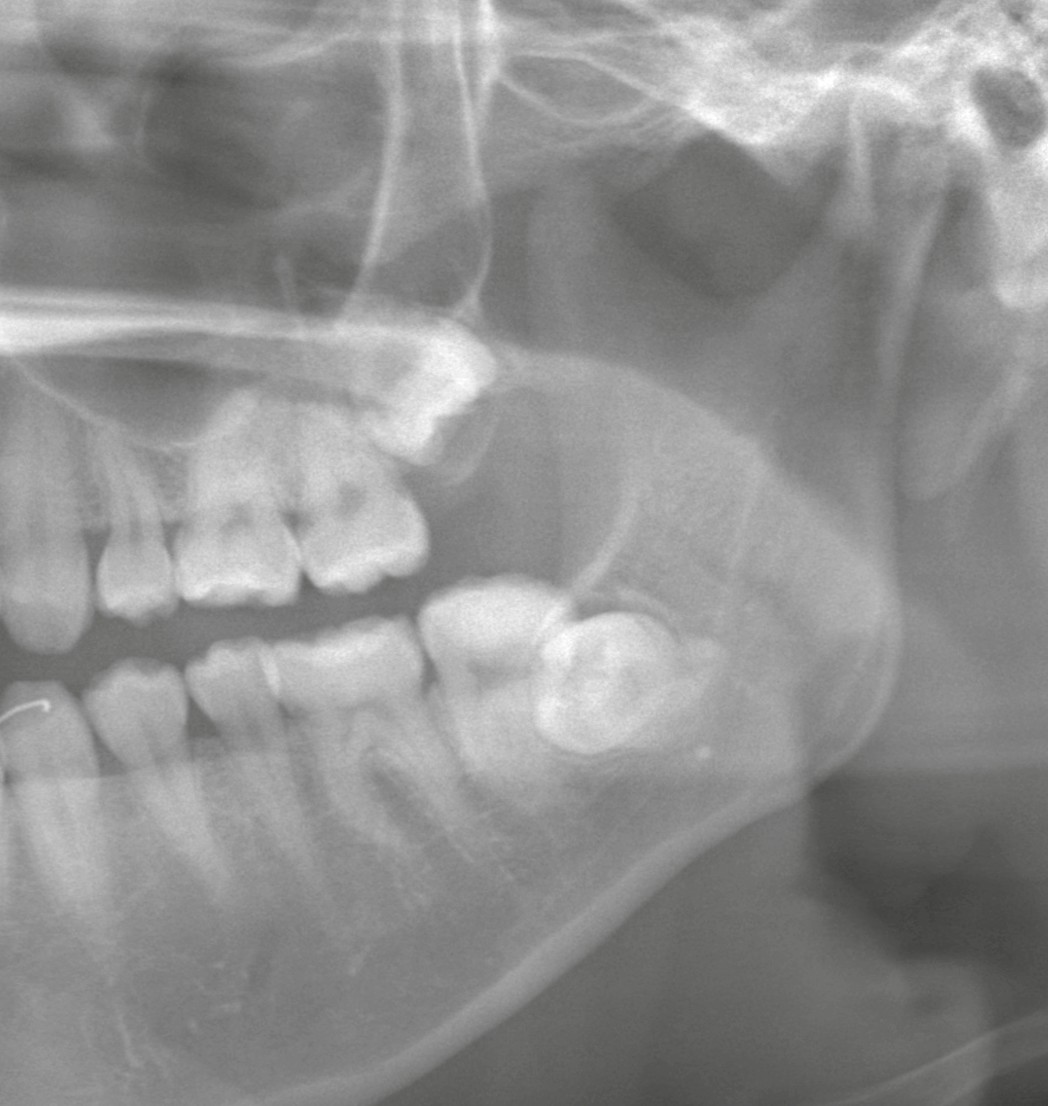

パノラマ所見 ― 歯根形態が読みにくい

まずはパノラマレントゲンを撮影。

パノラマ画像では、

・下顎の歯根形態がやや不明瞭

・歯根が単純ではなさそうな印象

・上顎は埋伏傾向が強い

という所見でした。

しかし、2D画像では歯根の湾曲や神経との立体的位置関係は正確に把握できません。

そこでCT撮影を実施しました。